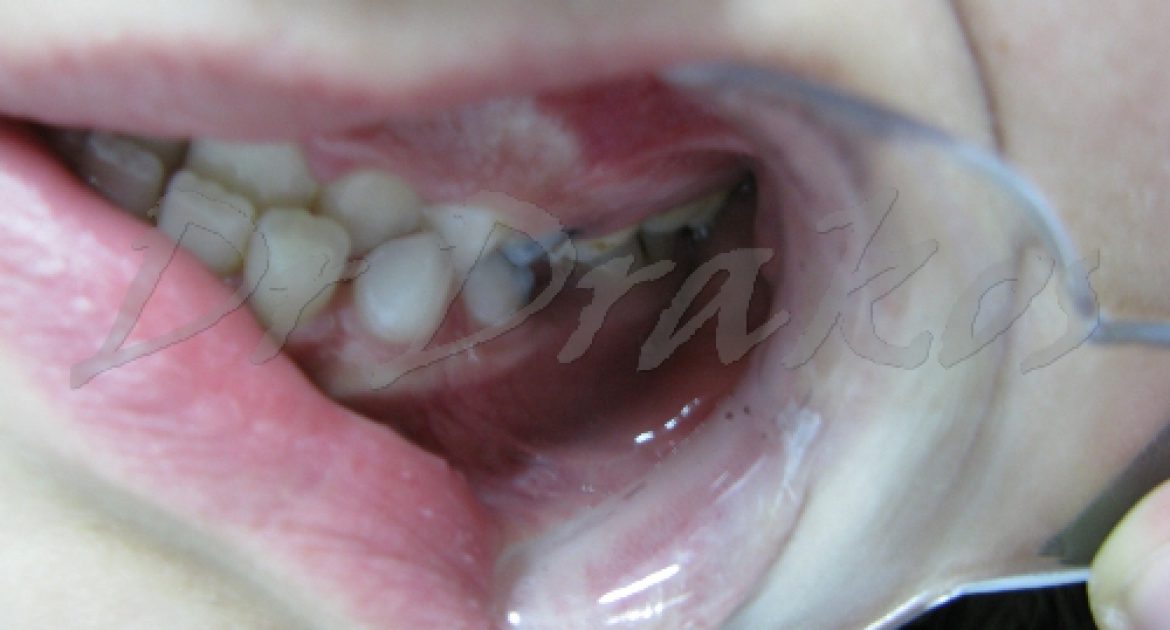

Κορίτσι (15 ετών)

Θεραπεία χωρίς εξαγωγές Διάρκεια Θεραπείας: 16 μήνες